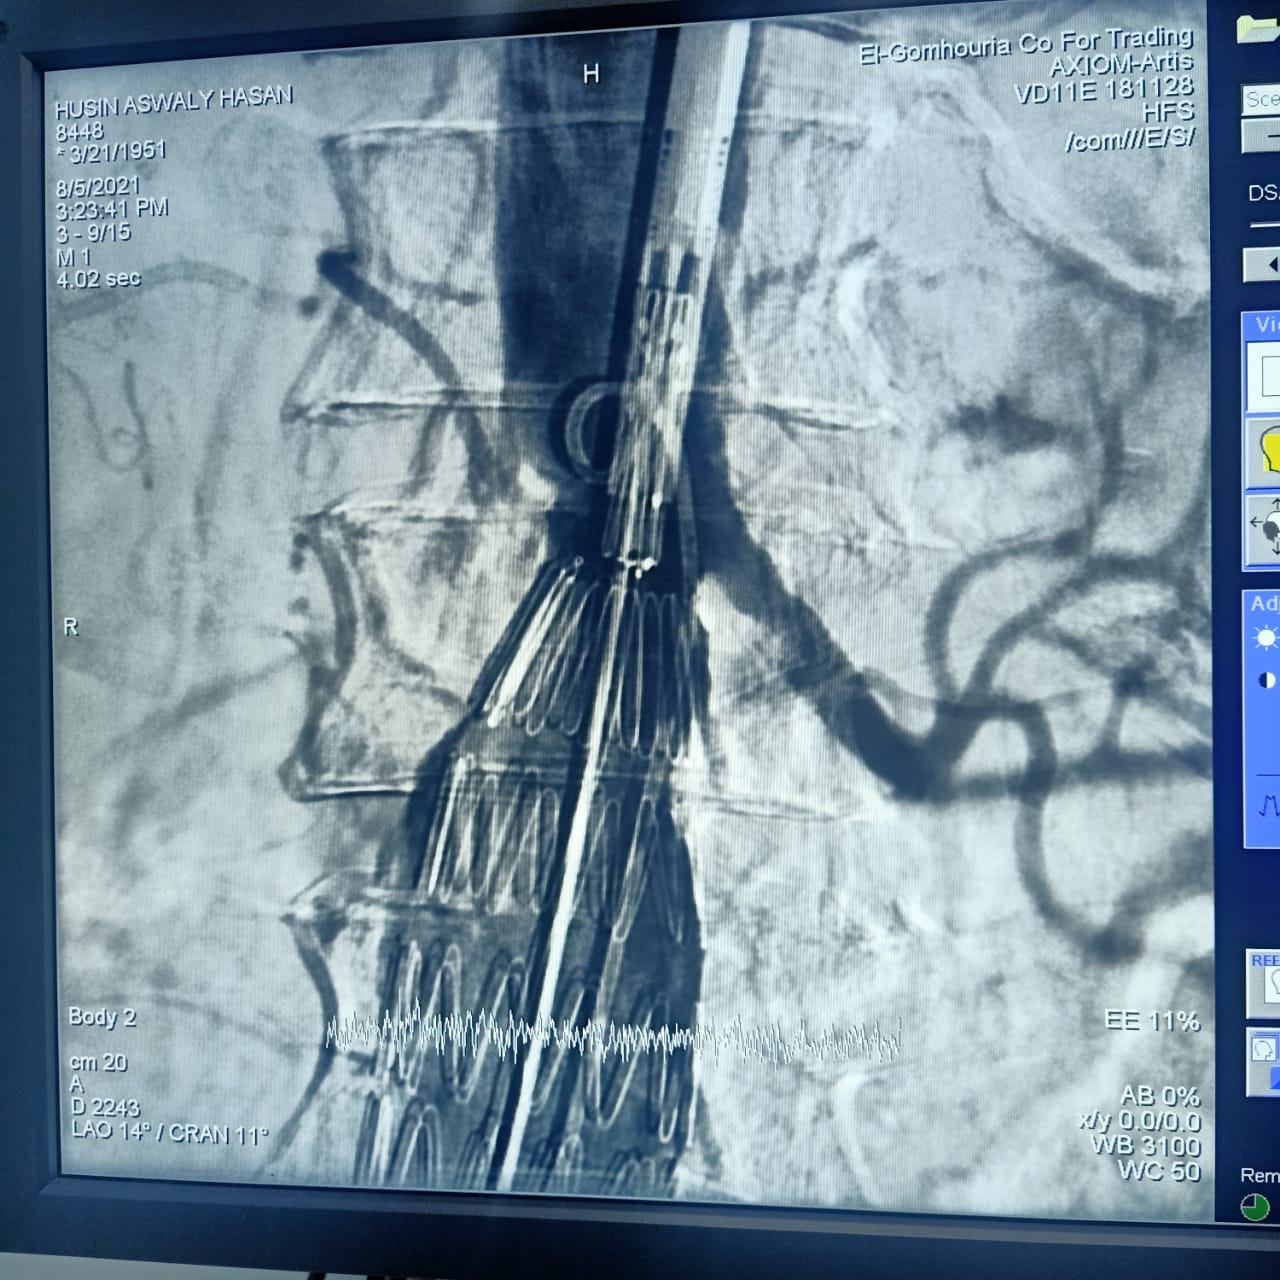

وأشارت هيئة الرعاية الصحية، أن CERAB، EVAR هي من أحدث التقنيات العلاجية لأمراض تمدد وانسداد الشريان الأورطي البطني والحرقفي (بدون جراحة)، من خلال علاج تمدد الشريان الأورطي البطني عن طريق القسطرة باستخدام تقنية الدعامات المغطاة EVAR، وكذلك علاج انسداد الشريان الأورطي البطني والحرقفي عن طريق القسطرة باستخدام تقنية الدعامات المغطاة ذات المقاومة العالية للانسداد CERAB، وذلك وفقًا لأحدث ممارسات الصحة العالمية.

وتابعت الهيئة: أن العملية الأولى كانت لعلاج مُسِّن يبلغ من العمر 70 عامًا يعاني من تمدد بالشريان الأورطي البطني وتم علاجه باستخدام تقنية الدعامات المغطاة EVAR، بينما كانت العملية الثانية لعلاج مريض يبلغ من العمر 65 عامًا باستخدام تقنية الدعامات المغطاة المقاومة للانسداد CERAB، مشيرة إلى استقرار الحالة الصحية للمريضين وإجراء العمليات بنجاح على يد أمهر الأطقم الطبية والتمريضية في مستشفى طيبة التخصصي بالأقصر.